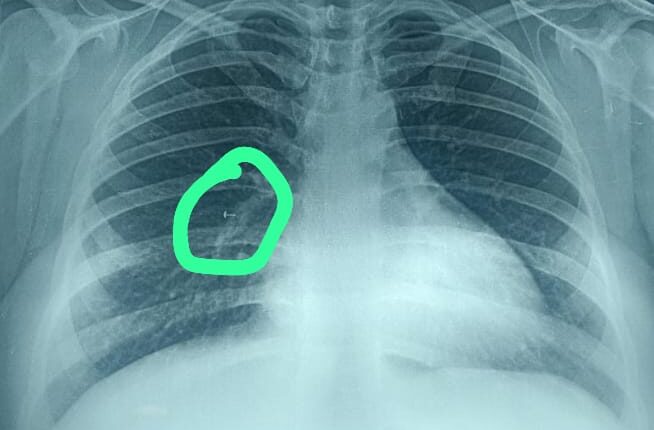

बरखा देवी, जो लगभग तीस साल की गृहिणी हैं (गोपनीयता के लिए नाम बदल दिया गया है) ने कुछ महीने पहले गलती से अपनी नाक की पिन में पेंच फंसा लिया था। घटना, जिसे शुरू में खारिज कर दिया गया था, ने एक नाटकीय मोड़ ले लिया जब कई महीनों बाद नाक की चोट के बाद एक एक्स-रे से उसके फेफड़े के अंदर फंसी वस्तु की उपस्थिति का पता चला।

स्थिति की जटिलता तब और बढ़ गई जब पहले उसका इलाज कर रहे डॉक्टर द्वारा पारंपरिक ब्रोंकोस्कोपी का उपयोग करके वस्तु को निकालने का प्रयास विफल हो गया और फिर उसे मेडिका सुपरस्पेशलिटी अस्पताल, कोलकाता के श्वसन चिकित्सा विभाग के निदेशक डॉ देबराज जश के पास भेजा गया।